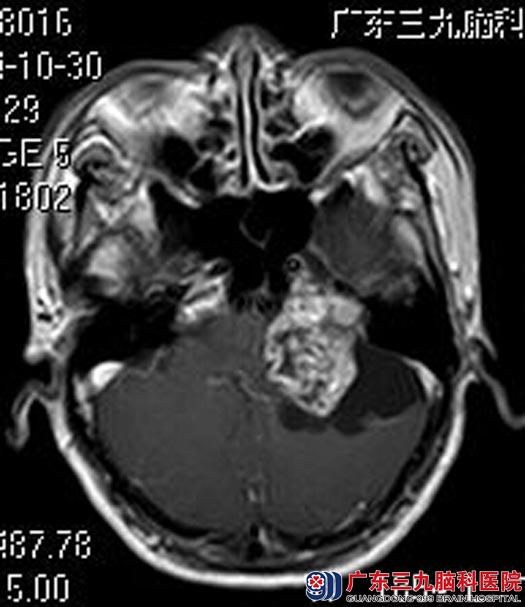

在广东三九脑科医院进一步MR检查发现:左侧桥小脑角一团块状囊实性占位性病变,大小约4.26×3.35×3.06cm,考虑听神经瘤可能性大。